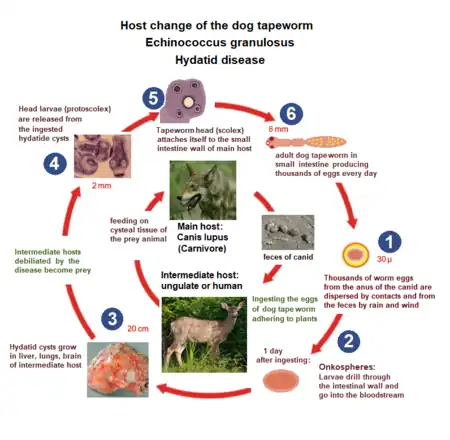

The lifecycle of E. granulosus involves dogs and wild carnivores as a definitive host for the adult tapeworm.[4] Definitive hosts are where parasites reach maturity and reproduce. Wild or domesticated ungulates, such as sheep, serve as an intermediate host.[4] Transitions between life stages occur in intermediate hosts. The larval stage results in the formation of echinococcal cysts in intermediate hosts.[4] Echinococcal cysts are slow growing,[4] but can cause clinical symptoms in humans and be life-threatening.[3] Cysts may not initially cause symptoms, in some cases for many years.[4] Symptoms developed depend on location of the cyst, but most occur in the liver, lungs, or both.[3]

E. granulosus requires two host types, a definitive host and an intermediate host. The definitive host of this parasite are dogs and the intermediate host are most commonly sheep, however, cattle, horses, pigs, goats, and camels are also potential intermediate hosts.[5] Humans can also be an intermediate host for E. granulosus, however this is uncommon and therefore humans are considered an aberrant intermediate host.[5] Echinococcus granulosus is ingested and attaches to the mucosa of the intestines in the definitive host and there the parasite will grow into the adult stages.[6] Adult E. granulosus release eggs within the intestine which will be transported out of the body via feces.[6] When contaminated waste is excreted into the environment, intermediate host has the potential to contract the parasite by grazing in contaminated pasture, perpetuating the cycle.[5][7]

Echinococcus granulosus is transmitted from the intermediate host (sheep) to the definitive host (dogs) by frequent feeding of offal, also referred to as "variety meat" or "organ meat". Consuming offal containing E. granulosus can lead to infection; however, infection is dependent on many factors.[3]